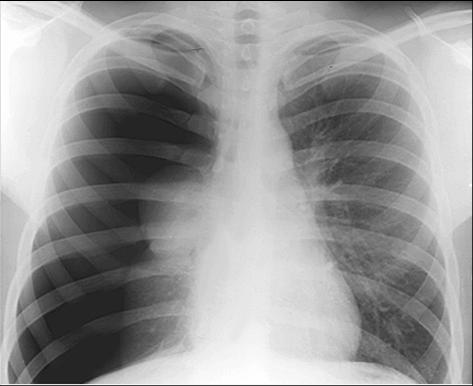

照片名称:正常x光胸片